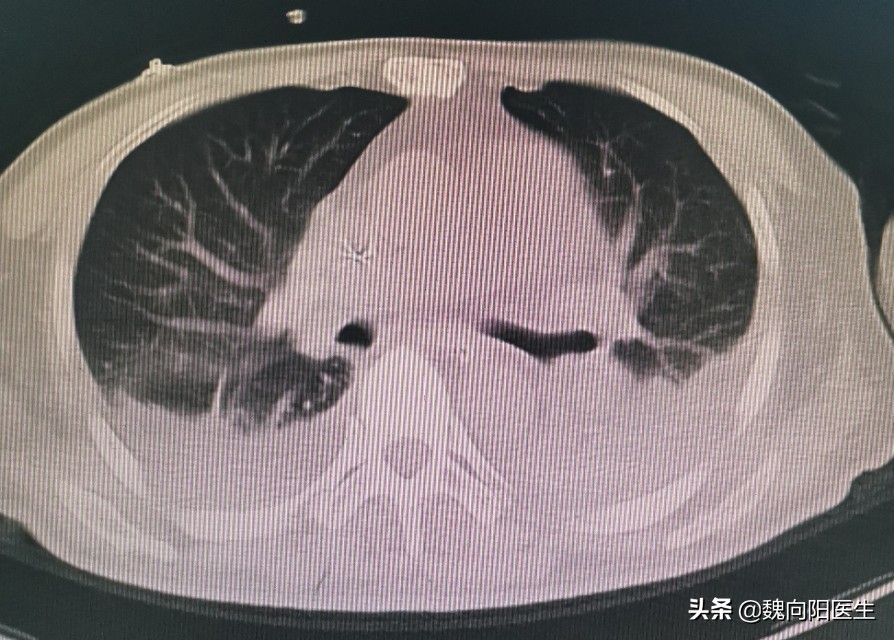

也不是所有的肺炎都会出现肺部的异常呼吸音(湿罗音和干罗音)。必要的时候的时候也需要查胸片或者胸部CT!